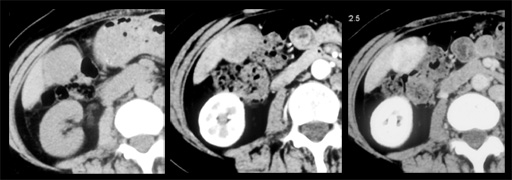

図1

図1 図2 T2WI・DWI